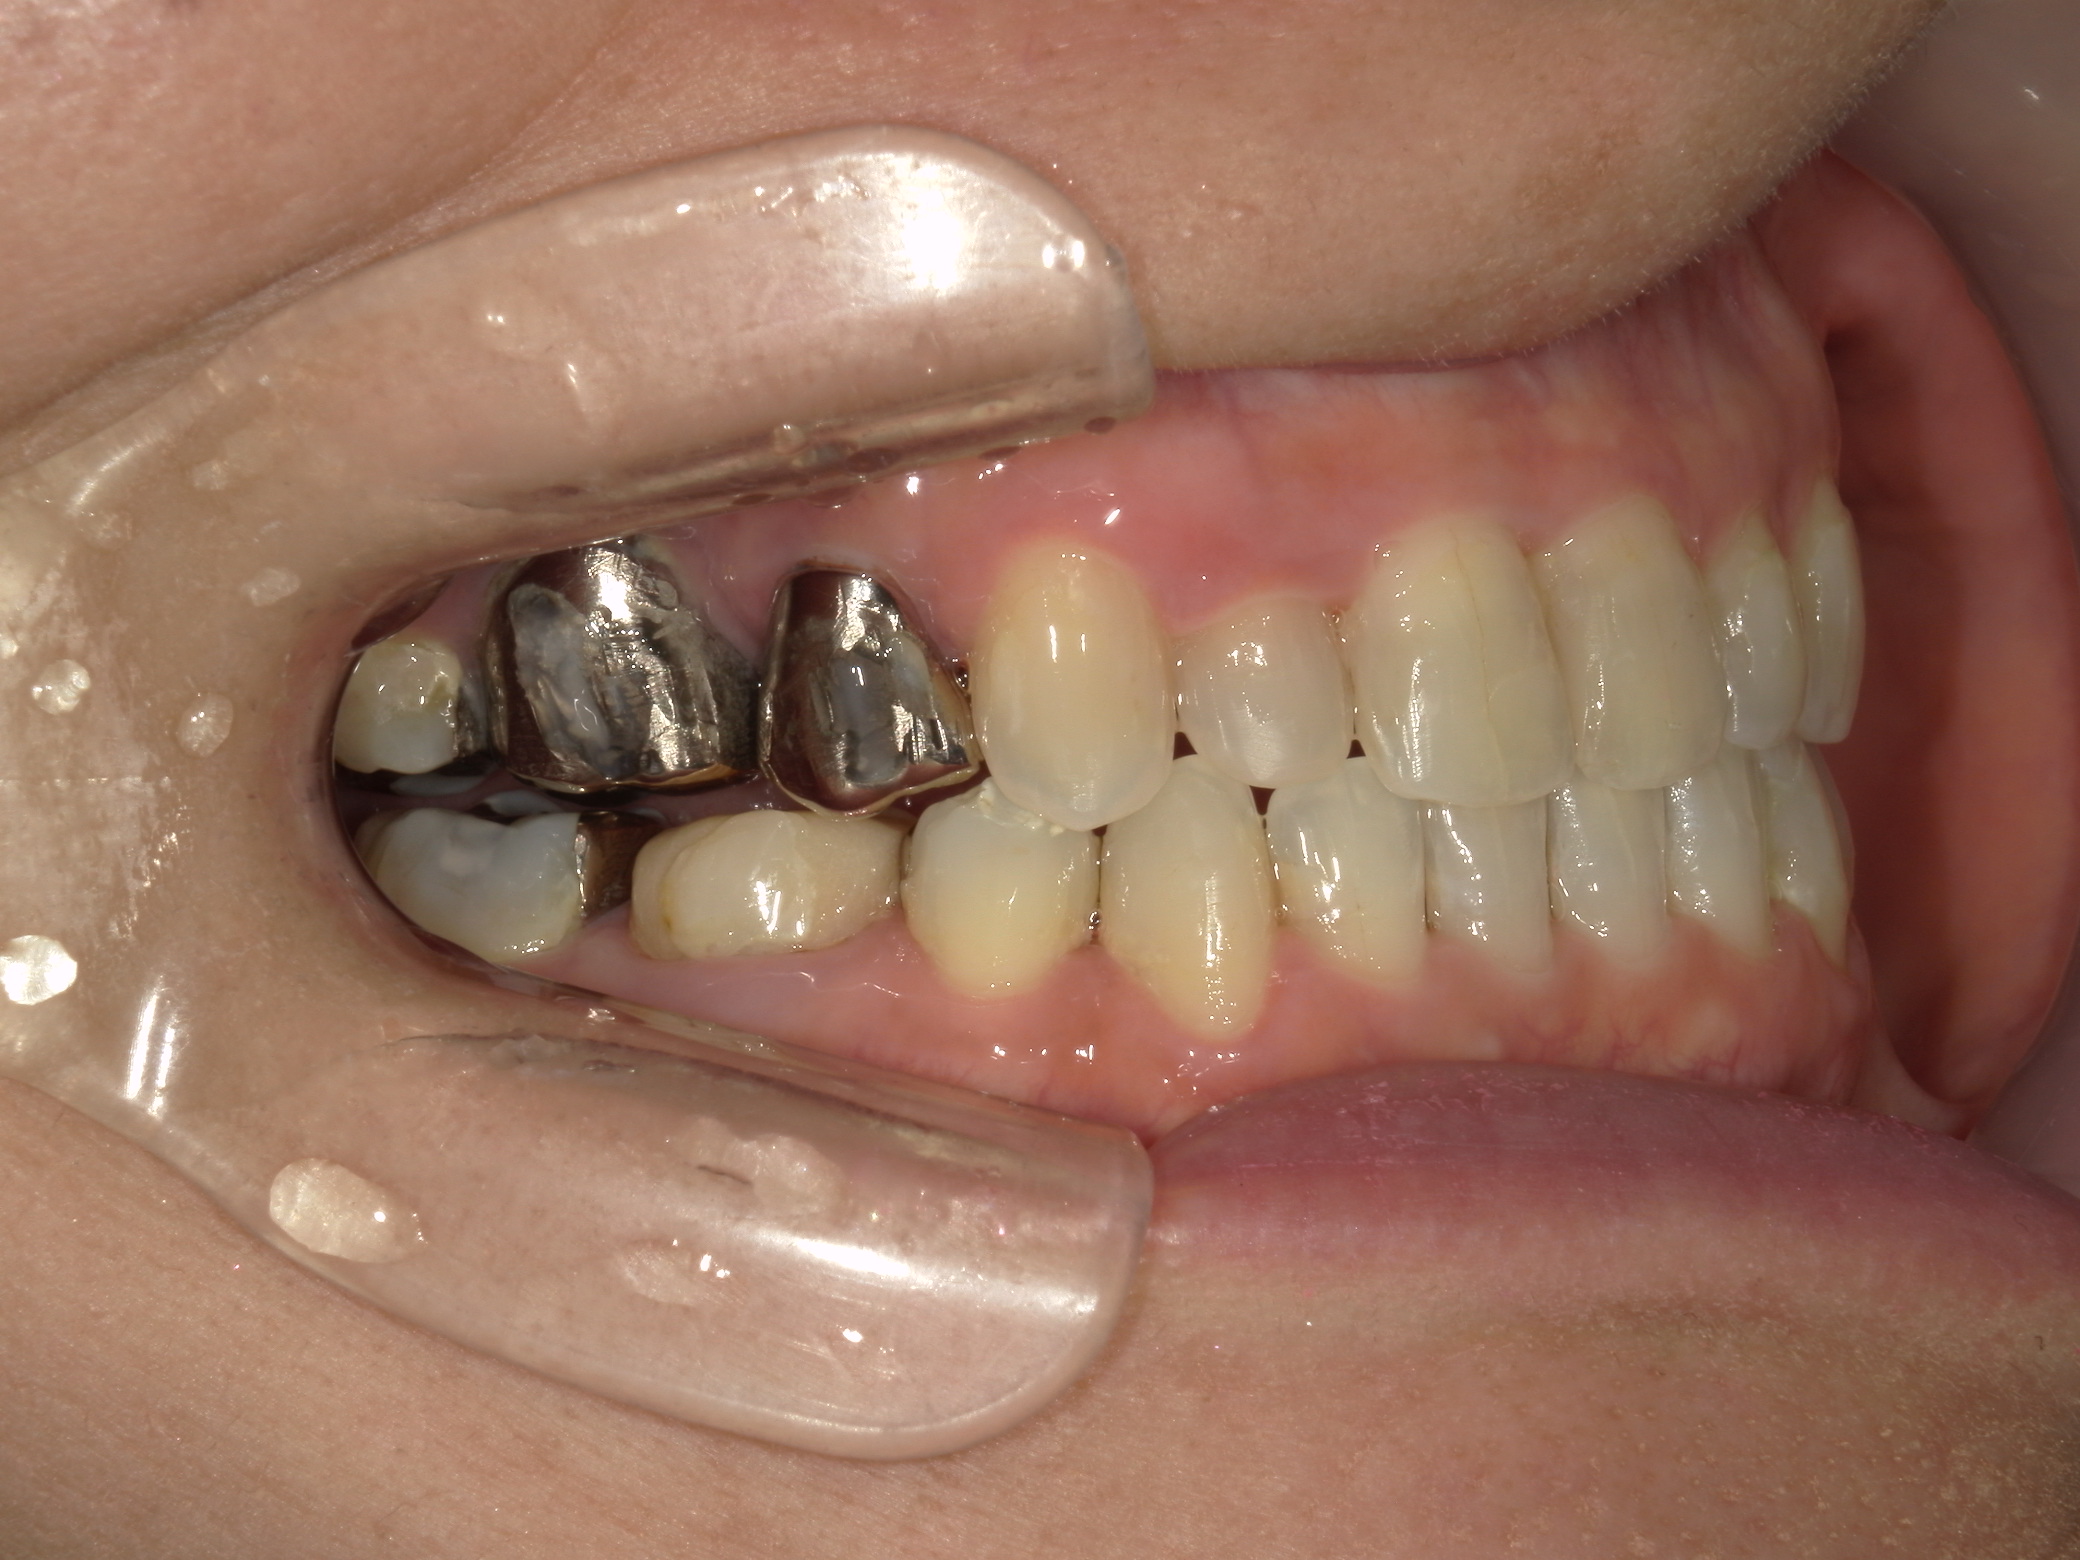

②右上前歯が内側に入っているため、歯列に入る隙間を作るためにワイヤー矯正を併用し、右上前歯を出しました。

③矯正装置を除去し、インビザライン矯正で歯列を整えました。